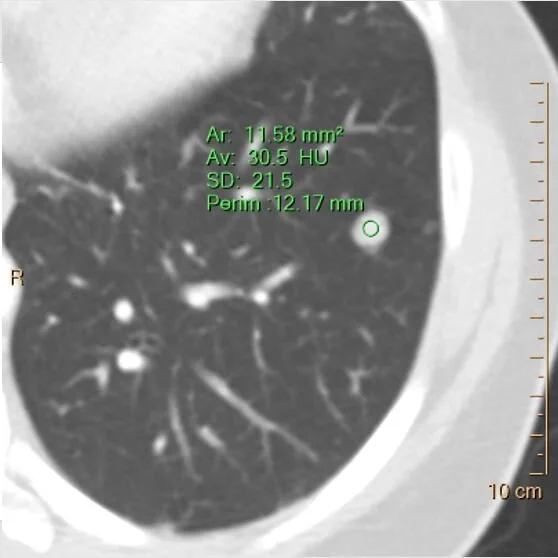

Nodule is about 30 HU on conventional CT…

…and about 26 HU on virtual non-contrast. So there is no enhancement.